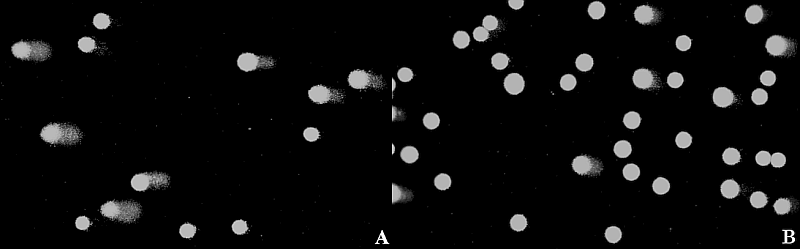

Введение Лесные и торфяные пожары - масштабное биосферное явление, служащие источником загрязнения воздуха сложной смесью продуктов горения растительной биомассы и органических отложений. Различные газы, полидисперсные твердые микро- и наночастицы и летучие органические соединения, образующиеся в этом процессе, рассматриваются как потенциально опасные поллютанты. Их воздействию подвергается все больше людей, поскольку масштабность природных пожаров в районах крупных мегаполисов возрастает, что определяет необходимость разработки соответствующих лечебных и профилактических мер, направленных на предупреждение и купирование патогенетических эффектов экспозиции дымами на здоровье человека [1, 19]. Эпидемиологические исследования свидетельствуют о поражениях дыхательной и сердечно-сосудистой систем, а также возникновении цереброваскулярных, гемостатических и репродуктивных нарушений у лиц, находящихся в зонах задымленности [1, 15]. Вместе с этим открытым остается вопрос о генотоксических эффектах и отдаленных генетически обусловленных последствиях воздействия задымлений. В предыдущих исследованиях было показано, что экспозиция торфяным дымом беременных крыс вызывает эмбриотоксические эффекты и нарушения постнатального развития у потомства. Анксиолитик афобазол, обладающий цитопротекторными, антитератогенными и антимутагенными свойствами, значимо снижал выявленные негативные эффекты [2, 3]. В экспериментах с экспозицией табачным дымом была показана сопряженность эмбриопротекторных и антигенотоксических эффектов афобазола [1]. Целью настоящего исследования явилась оценка поврежденности ДНК в клетках плацент и эмбрионов крыс, подвергнутых принудительной экспозиции торфяным дымом, и возможности их коррекции афобазолом. Материалы и методы Исследования проводили на беспородных белых крысах массой 240-270 г (питомник РАМН «Столбовая»). Животных содержали в условиях вивария ФГБНУ «НИИ фармакологии имени В.В. Закусова» при 12-часовом режиме на стандартном сбалансированном брикетированном корме, со свободным доступом к воде и пище, при естественной освещенности, температуре воздуха 20-21 °С. Все эксперименты проводили в соответствии с международными правилами (European Communities Council Directive of November 24,1986 (86/609/EEC)) и правилами работы с животными, утвержденными этической комиссией ФГБНУ НИИ фармакологии имени В.В. Закусова. Самцов и самок крыс ежедневно вечером ссаживали попарно в отдельные клетки. Утром после ссаживания у каждой крысы брали вагинальный мазок. Ссаживание прекращали при обнаружении сперматозоидов в вагинальных мазках. День обнаружения сперматозоидов рассматривали как первый день беременности. Животных с 1-го по 13-й день беременности подвергали принудительному ингаляционному воздействию торфяного дыма с использованием оригинальной установки в пластиковых камерах объемом 72 дм3. В камеры помещали по 5-6 животных одновременно. Задымление камеры проводили путем вдувания дыма от четырех последовательно сгорающих бумажных гильз (0,46 г каждая), наполненных смесью, состоящей из 70 % торфа и 30 % древесной массы (производитель ООО «Эксторф»). Время сгорания каждой гильзы составляло 6 минут, общий срок экспозиции торфяным дымом - 44 минуты. Афобазол (фармакологическая субстанция, синтезированная в НИИ фармакологии имени В.В. Закусова) в виде водного раствора вводили перорально в дозах 1 и 10 мг/кг ежедневно, непосредственно перед экспозицией торфяным дымом. Интактных животных подвергали аналогичным процедурам без вдувания в камеры торфяного дыма. Каждая группа включала 5-6 животных. На 13-й день беременности через 30 минут после обработки торфяным дымом животных умерщвляли. От каждой самки отбирали по 4 плаценты и 4 эмбриона, каждый из которых разделяли на туловище и голову. Оценку ДНК-повреждений в клетках плаценты и эмбрионов проводили методом ДНК-комет в щелочной версии в соответствии с рекомендациями [1, 16]. Образцы плацент, голов и туловищ эмбрионов помещали в стеклянные пробирки с охлажденным до 4 °С фосфатно-солевым буфером (ФСБ), содержащим 20 mM EDTA-Na2, и 10 % ДМСО [рН 7,5] и тщательно раздавливали тефлоновым пестиком. Пробирки выдерживали 5 минут при комнатной температуре для осаждения крупных фрагментов тканей. Суспензии клеток в объеме 60 мкл вносили в пробирки с 240 мкл 1 % раствора легкоплавкой агарозы в ФСБ, подогретом до 36 °С (микротермостат «Термит», Россия), и ресуспендировали. Затем 60 мкл раствора агарозы с клетками наносили на предварительно покрытые 1 % универсальной агарозой предметные стекла, покрывали покровным стеклом и помещали на лед. На каждый образец плаценты, головы и туловища эмбрионов готовили один микропрепарат (всего 88 микропрепаратов). Далее все операции проводили в затемненном помещении при желтом свете. После затвердевания агарозы (около 5-10 минут) покровные стекла осторожно удаляли, микропрепараты помещали в стеклянную кювету (тип Шиффендекер), заливали предварительно охлажденным до 4 °С лизирующим буфером (10 mM Tris-HCl (pH 10), 2,5 M NaCl, 100 mM EDTA-Na 2,1 % TritonX-100, 10 % ДМСО) и инкубировали 1 час. После микропрепараты переносили в охлажденный до 4 °С буфер для электрофореза (300 mM NaOH, 1 mM EDTA-Na2 (pH > 13)) и инкубировали в течение 20 минут для реализации щелочно-лабильных сайтов и щелочной денатурации ДНК. После микропрепараты переносили в камеру для электрофореза (SubCell GT, Bio-Rad), заполненную свежим охлажденным буфером, и проводили электрофорез в течение 20 минут при напряженности поля 1 V/cm и силе тока ~300 mA. По окончании электрофореза микропрепараты переносили в стеклянную кювету, отмывали в течение 10 мин в ФСБ и фиксировали в 70 % растворе этилового спирта в течение 15 минут. После фиксации микропрепараты высушивали и хранили до анализа при комнатной температуре. Непосредственно перед микроскопированием препараты окрашивали флуоресцирующим красителем SYBR Green I (1 : 10000 в ТЕ-буфере (рН 8,5) с 50 % глицерином) в течение 30 минут в темноте. Цифровые изображения с микропрепаратов получали на эпифлуоресцентном микроскопе Микмед-2 12T («Ломо», Россия), совмещенном с цифровой камерой высокого разрешения (VEC-335, ЭВС, Россия), при увеличении × 200 (рис. 1). С полученных на каждый микропрепарат 10-15 изображений в программной среде CASP 1.2.2 анализировали не менее 100 ДНК-комет. В качестве показателя поврежденности ДНК использовали процентное содержание ДНК в хвосте ДНК-комет (% ДНК в хвосте). Перед статистической обработкой полученных данных выборки в группах проверялись на нормальность и гомогенность дисперсий с использованием критерия Шапиро - Уилка и критерия Барлетта соответственно. Поскольку распределение в группах отличалось от нормального и были выявлены различия в дисперсиях, в соответствии с рекомендуемыми подходами к статистической обработке данных метода ДНК-комет проводили логарифмическое преобразование исходных показателей с последующим анализом с использованием параметрического критерия Даннета (Moller P. et al., 2014). Различия считали статистически значимыми при p < 0,05. Результаты и обсуждение У контрольных животных уровень ДНК-повреждений, оцениваемый по показателю «% ДНК в хвосте», в клетках плаценты составил 3,1 [1, 9; 5, 3] (Median (Q25 %; Q75 %), табл. 1). В клетках головы и туловища эмбрионов оцениваемый показатель зарегистрирован на уровне 2,2 [1, 3; 3, 3] и 2,1 [1, 2; 3, 6] % ДНК в хвосте соответственно. У крыс, подвергнутых воздействию торфяного дыма, выявлено статистически значимое увеличение уровня ДНК-повреждений в исследуемых тканях. В голове и туловище эмбрионов уровень ДНК-повреждений по сравнению с контрольными значениями возрос в 4,4 раза, в плаценте - в 4,1 раза. В группе животных, получавших афобазол в дозе 1 мг/кг, выявлено статистически значимое снижение индуцированных торфяным дымом ДНК-повреждений во всех исследуемых тканях. Генотоксический эффект в голове и плаценте снизился в 2,4-2,6 раза, в плаценте - в 1,7 раза. Антигенотоксические эффекты афобазола при его использовании в дозе 10 мг/кг оказались сходны. Таким образом, установлено, что экспозиция торфяным дымом приводит к индукции повреждений ДНК в клетках плаценты и эмбрионов крыс. Генотоксические эффекты в исследованных тканях оказались сопоставимы, более чем четырехкратное превышение спонтанного уровня ДНК-повреждений. Вместе с тем анализ индивидуальных данных демонстрирует высокую вариабельность выявленных эффектов как между животными, так и между плацентами и эмбрионами одного животного (рис. 2). В большинстве образцов уровень ДНК-повреждений в клетках плаценты оказался выше по сравнению с клетками соответствующего эмбриона. При этом выявлены пары плацента/эмбрион со значимо более выраженным эффектом в клетках плаценты и пары, для которых эти различия минимальны. Наблюдаемые внутрииндивидуальные различия могут быть связаны с так называемым феноменом внутриутробного положения (intrauterine position). Так, была показана более высокая устойчивость эмбрионов, расположенных в срединной части рога матки, к действию ионизирующего излучения, гипоксии и ряда химических агентов [11, 21, 22]. Анализ имеющихся на сегодня экспериментальных данных позволяет предположить три возможных механизма реализации генотоксических эффектов торфяного дыма. Во-первых, экспозиция торфяным дымом может приводить к гипоксическим состояниям матери и эмбрионов, сопровождающимся гиперпродукцией активных форм кислорода (АФК) в клетках и окислительным повреждением ДНК [9, 14]. Во-вторых, торфяной дым содержит значительные концентрации мутагенных и канцерогенных соединений, в первую очередь полициклических ароматических углеводородов (ПАУ), свободно проникающих через плацентарный барьер [10, 20]. В этой связи стоит отметить данные эпидемиологического исследования, в котором была показана связь между уровнем специфических для ПАУ ДНК-аддуктов в клетках материнской и пуповинной крови и риском развития тревожно-депрессивных расстройств в возрасте 6-7 лет [17]. Эти данные являются важным свидетельством в поддержку разрабатываемой концепции патогенетической роли первичных ДНК-повреждений [4] в том числе в нарушениях анте- и постнатального развития. В-третьих, в торфяном дыме содержатся твердые микро- и наночастицы размером от 10 мкм до < 100 нм. Накапливаясь в альвеолах материнского организма, они способны попадать в системный кровоток, преодолевать плацентарный барьер и достигать тканей эмбрионов, проявляя при этом генотоксическую активность посредством активации свободнорадикальных процессов [12, 13]. Очевидно, что генотоксические эффекты торфяного дыма реализуются по нескольким путям одновременно и являются следствием суммарного воздействия всех факторов, в существенной мере реализующих генотоксический потенциал через продукцию генотоксических АФК. Отсюда антигенотоксические свойства афобазола логично объясняются его антирадикальной/антиоксидантной активностью [7, 8]. Связь между генотоксическими поражениями и болезнями хорошо известна [4]. Исследование генотоксических эффектов торфяного дыма является важным для разработки мер и средств профилактики отдаленных патогенетических проявлений. В настоящем исследовании установлено, что антимутаген афобазол снижает индуцируемые экспозицией торфяным дымом ДНК-повреждения в клетках плаценты и эмбриональных тканей крыс. Афобазол, как было показано выше, не демонстрировал per se генотоксических свойств ни в одном из предъявленных тестов, в том числе в тесте ДНК-комет в эмбриональных тканях [2, 3]. Протекторные эффекты афобазола оказались сходны для обеих использованных доз и исследованных тканей - 53-60 % снижение уровня индуцированных ДНК-повреждений. Анализ индивидуальных данных демонстрирует меж- и внутрииндивидуальные различия. Важно отметить, что для части эмбрионов наблюдалось снижение уровней ДНК-повреждений до спонтанного уровня. Таким образом, полученные в настоящем исследовании данные свидетельствуют о генотоксических эффектах в плаценте и эмбрионах крыс, подвергнутых экспозиции торфяным дымом. Анксиолитик афобазол, обладающий антимутагенными свойствами, снижает повреждения ДНК, индуцируемые торфяным дымом во всех исследованных тканях. При этом важно, что защитный эффект проявляется в том числе при использовании препарата в дозе 1 мг/кг, соответствующей терапевтической для человека [8]. В совокупности с данными предыдущих исследований [2, 3] вышеприведенные результаты определяют перспективность применения афобазола в качестве средства защиты от негативных эффектов торфяного дыма.About the authors